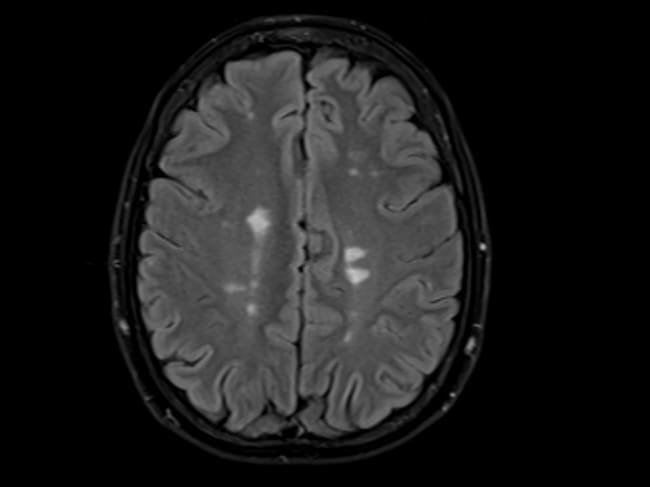

Un cerebro que muestra la esclerosis múltiple.Un estudio señala al virus de la enfermedad del beso como la causa principal. / Paul Biris (Getty Images)

La esclerosis múltiple es una enfermedad inflamatoria crónica del sistema nervioso central que ataca las vainas de mielina que protegen las neuronas del cerebro y la médula espinal.